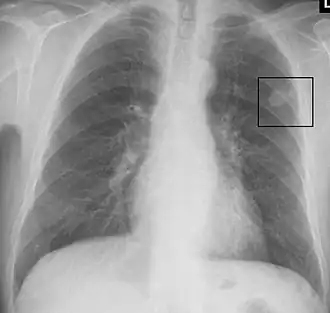

Обработанная цифровая рентгенограмма грудной клетки (лёгочные поля в позитивном изображении, с повышенной контрастностью).

Обработанная цифровая рентгенограмма грудной клетки (лёгочные поля в позитивном изображении, с повышенной контрастностью). Рентгенограмма грудной клетки в боковой проекции.

Некачественная рентгенограмма грудной клетки. Рентгенограмма грудной клетки, демонстрирующая солитарный лёгочный узел в верхней доле левого лёгкого.

Рентгенограмма грудной клетки, демонстрирующая солитарный лёгочный узел в верхней доле левого лёгкого.